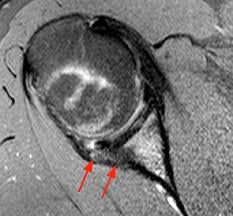

2.5 year old boy who won’t bear weight

Osteomyelitis

typical appearance and location for osteomyelitis.

Extension into the epiphysis is typical; may be seen with tumors but more common with osteomyelitis.

The diffuse sclerosis surrounding the lytic lesions represents typical host reaction to the infection.